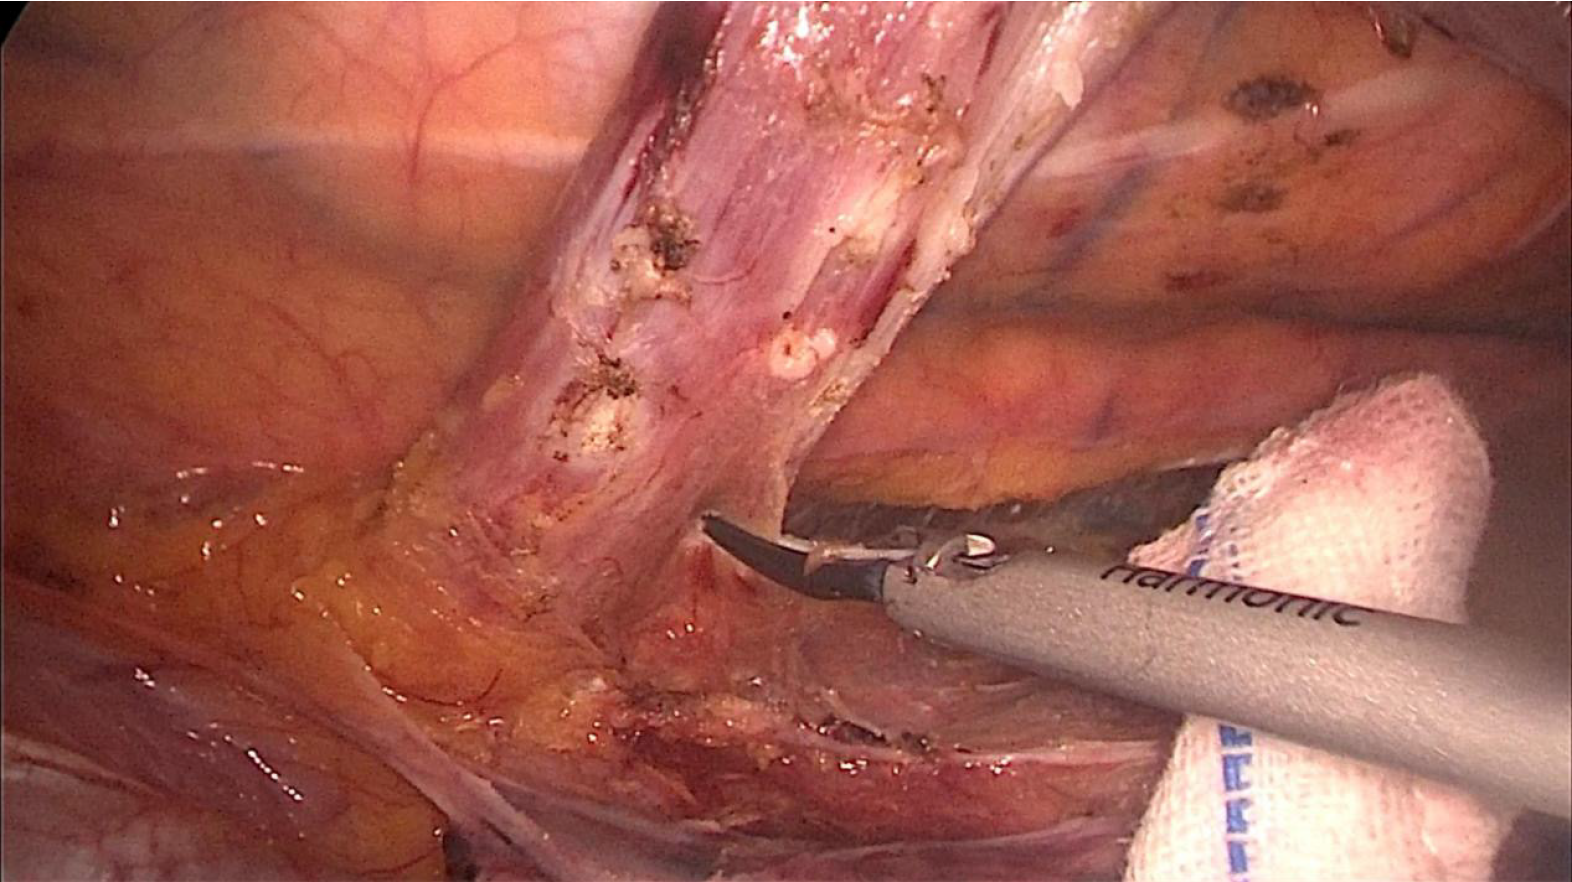

Figure 2

Figure 2  Intraoperative image of thoracoscopy-assisted ultrasonic scalpel resection.